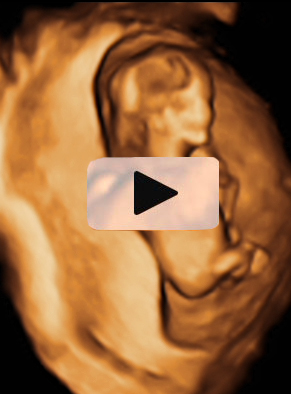

Ecografía 4D semana 11: Siameses unidos por el abdomen

La ecografía en 4D (vídeo) no deja lugar a dudas. Se trata de un embarazo de siameses de 11 semanas de gestación, que están unidos por la zona abdominal, ya que comparten una pequeña parte de hígado. La movilidad de los bebés es reducida, como vemos en las imágenes, debido a la unión de sus cuerpos. Uno de los hermanos (el de la derecha) mueve la cabeza hacia atrás, mientras las piernas se entrecruzan. Los especialistas siguen este tipo gestaciones muy de cerca y valoran la separación quirúrgica de los bebés, una vez que se produce el parto.